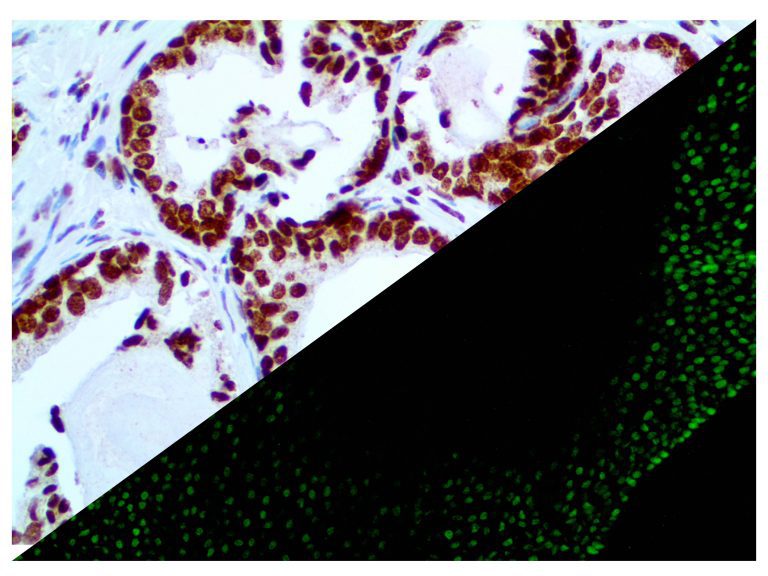

The first cytokines released are interleukin 1β (IL-1β) and tumor necrosis factor-α (TNF-α), which attract a variety of circulating white blood cells (WBCs) to the infection site, including neutrophils, monocytes, macrophages, and natural killer (NK) cells. This response, along with the antipathogenic chemicals released by these cells (i.e., complement), comprise the innate immune response. These cells directly attack the invading pathogen and also release additional cytokines, chief among them interleukin-1 and 6 (IL-6). IL-6 is essential for invoking the adaptive immune response, which calls T-cells, B-cells, and T helper (Th) cells to the infection site. IL-6 also stimulates further recruitment, proliferation and activation of macrophages.

It is the ICU physician who is most likely to witness one of the deadliest manifestations of the abnormal immunological response, the cytokine storm syndrome (CSS). This response is also referred to by some as the cytokine release syndrome (CRS). CSS is characterized by continuous activation and expansion of macrophage and lymphocyte populations, which secrete large amounts of cytokines, causing the cytokine storm. This massive cytokine release is akin to hemophagocytic lymphohistiocytosis (HLH) disease, a syndrome characterized by initial unchecked and persistent activation of cytotoxic T lymphocytes and NK cells.

This activation induces inflammatory monocytes to highly express IL-6, starting a localized and then systemic cascade effect that results in hyperproduction of IL-6, which accelerates the inflammatory process. Because IL-6 also increases vascular permeability, excessive levels cause blood vessels to become very leaky. This, along with clotting factors released from vascular endothelial cells, stimulates the coagulation cascade, resulting in microthrombosis (tiny clots), which leads to ischemia and tissue death of the kidney, intestines, heart, liver, brain and extremities.